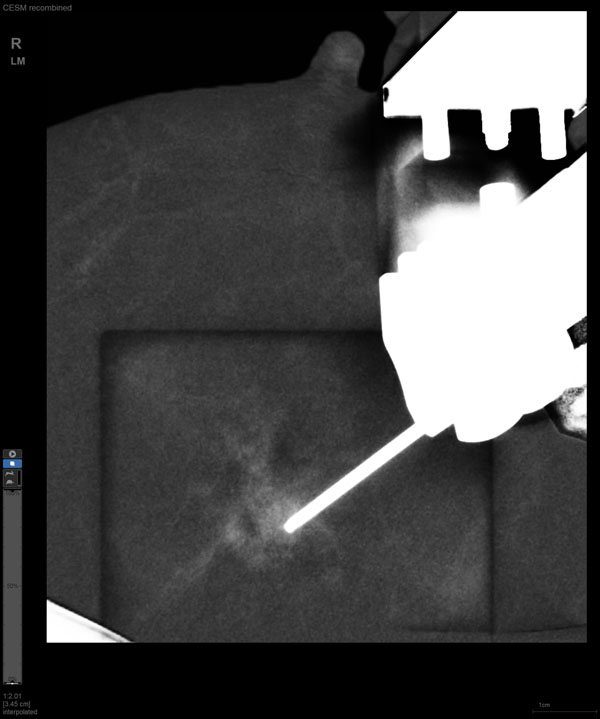

国内首台具有数字乳腺断层摄影(DBT)和CEM引导下穿刺功能的X线机

随着计算机技术发展和乳腺X线机硬件的提升,CEM与立体定向活检技术相结合的CEM引导下穿刺活检术开始在临床应用。与MRI引导的乳腺穿刺活检相比,CEM穿刺活检无需抗核磁耗材,成本更低,检查速度更快。据国外研究文献报道,CEM引导的穿刺活检有可能成为MRI引导的乳腺穿刺活检的有效替代方案。